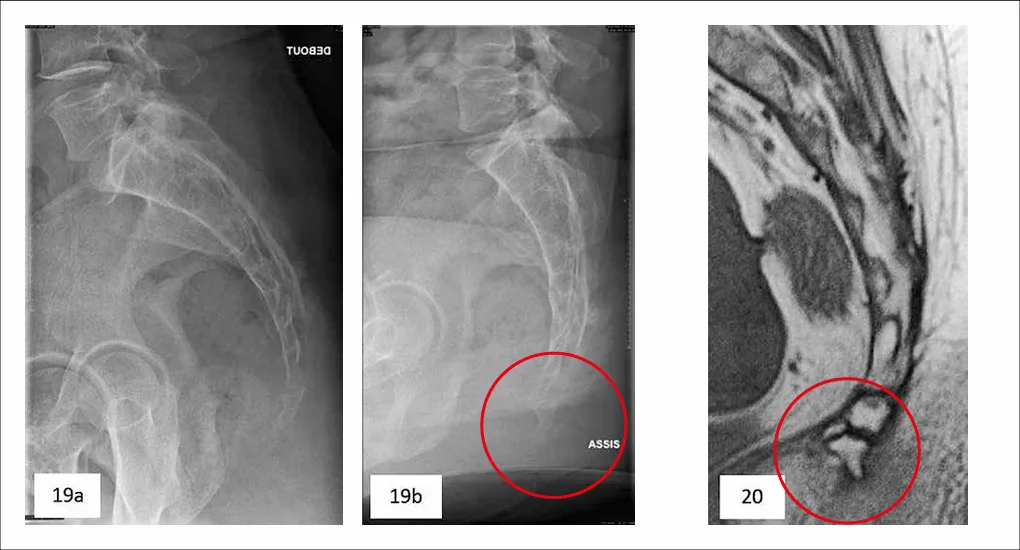

Outre les fractures, l’activité sportive peut être responsable de coccygodynies liées à une instabilité coccygienne par luxation (figures 19a et 19b), nécessitant un examen radiologique de profil en position debout puis assise, à une arthrose coccygienne ou à une épine coccygienne (92) pouvant engendrer une bursite (figure 20).

Figures 19a, 19b et 20 : luxation postérieure du coccyx [19a et 19b] (© Coll JM Didelot) et épine coccygienne [20] (92)